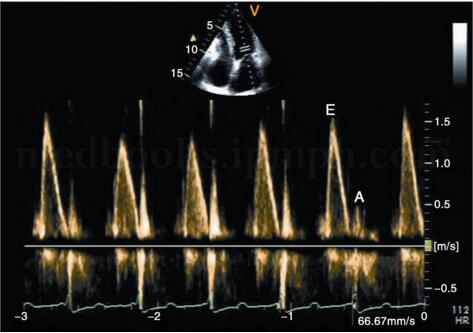

3﹒脉冲多普勒超声心动图 主要表现为左房室瓣口舒张早期前向血流速度明显增高、EF斜率快速下降、舒张晚期血流速度减慢,形成E峰高尖而A峰低小、E/A比值明显增大的图像,见图2‐1‐235。但此征象并不具有特异性,也可见于限制型心肌病或严重左房室瓣反流。缩窄性心包炎患者可出现呼气时二尖瓣E峰增高,吸气时下降,见图2‐1‐236;吸气时主动脉血流速度也明显减低,呼气时血流速度增快。

图2‐1‐235 缩窄性心包炎患者,二尖瓣血流频谱E峰 明显升高,E/A增大